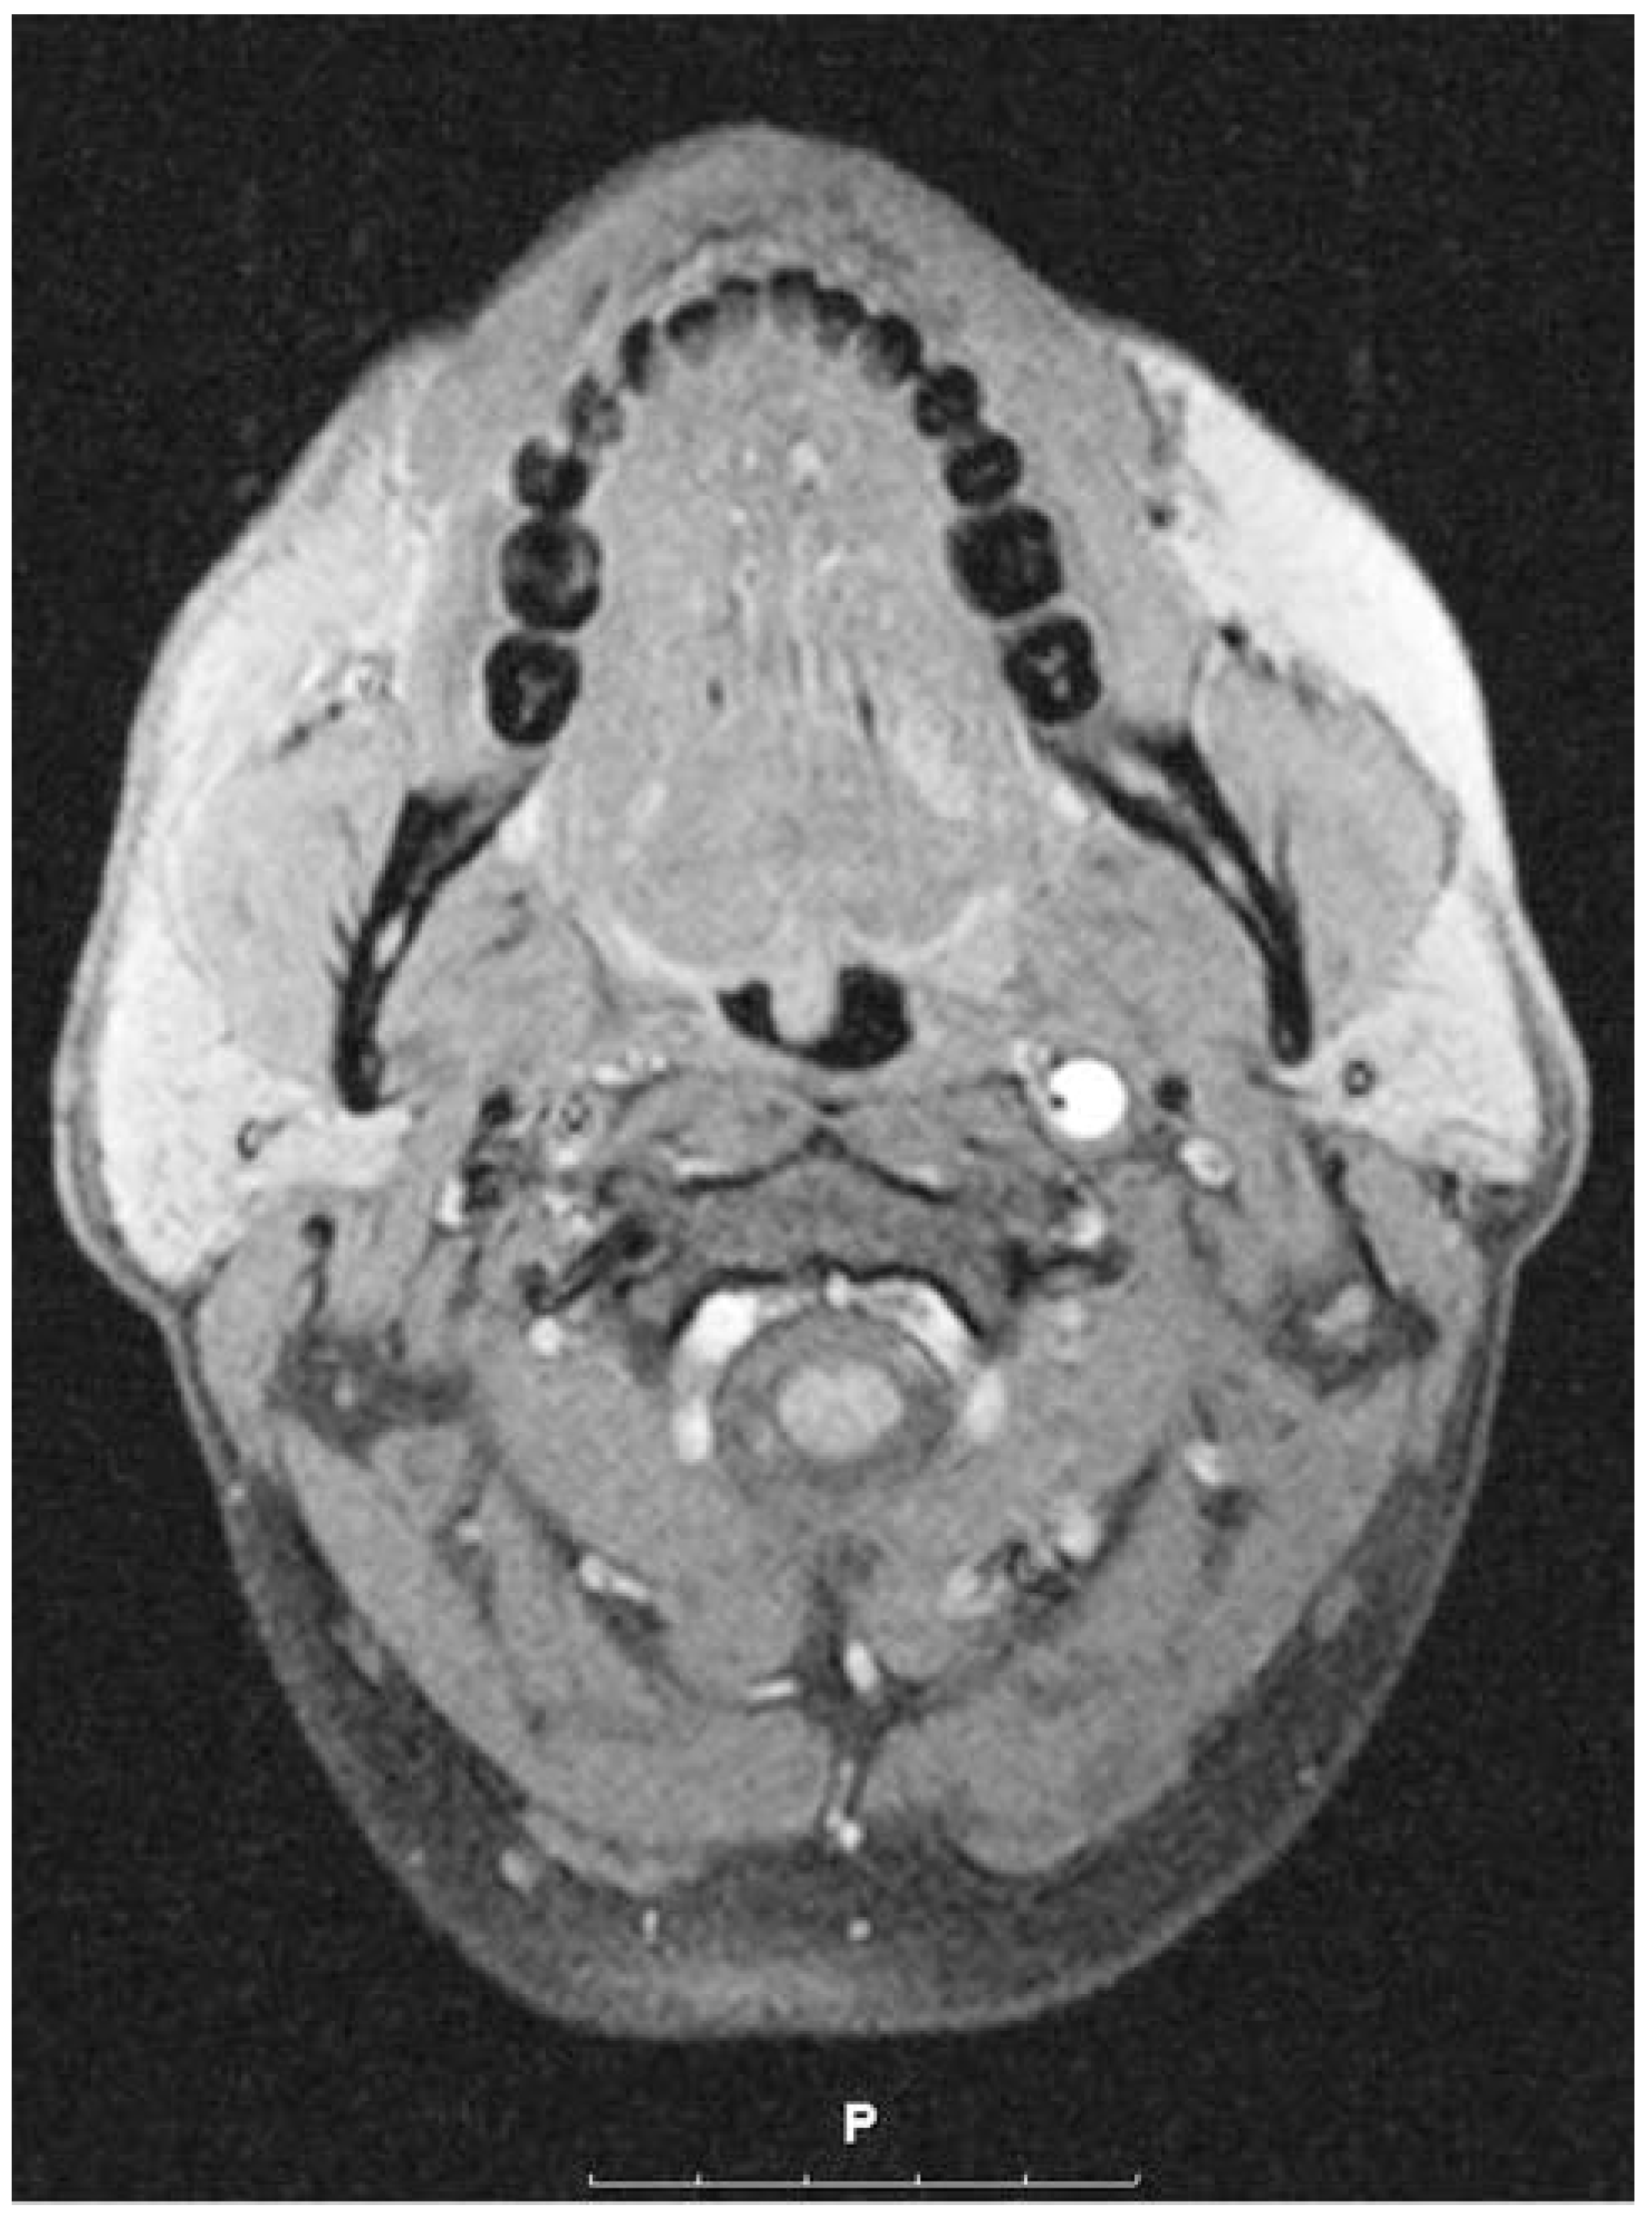

Diagnosis